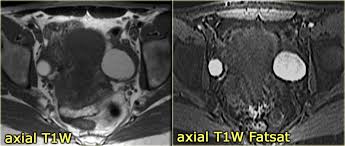

Page 52 Wjols Journal Of Laparoscopic Surgery from www.laparoscopyhospital.com These tumors or cysts can contain different kinds of benign. Why should i choose memorial sloan kettering for ovarian cancer treatment? Symptoms become more noticeable as the cancer progresses. Ovarian cancers were previously believed to begin only in the ovaries, but recent evidence suggests that many ovarian cancers may actually start in it is often called a dermoid cyst because its lining is made up of tissue similar to skin (dermis). The symptoms of ovarian cancer, though vague, may be more extensive than those of ovarian cysts. Surgeons like to remove them because they can burst. A neurosurgeon may need to remove them if they cause problems. They are often harmless and require no treatment.

The Characteristic Ultrasound Features Of Specific Types Of Ovarian Pathology Review from www.spandidos-publications.com How is ovarian cancer diagnosed? When cysts do cause pain, it is typically felt in the lower abdomen. Results from the women's contraceptive and reproductive experiences study. The symptoms of ovarian cancer, though vague, may be more extensive than those of ovarian cysts. Ovarian torsion is another uncommon problem of ovarian cysts. Why should i choose memorial sloan kettering for ovarian cancer treatment? Surgeons like to remove them because they can burst. Ovarian cysts and breast cancer: